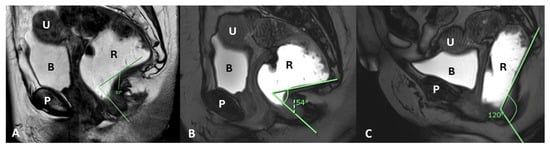

| Anorectal Angle | Angle between the posterior distal rectum and the anal canal’s central axis | Reflects the levator ani muscle function during contraction | 108–127° at rest, decreases by 15–20° during contraction |